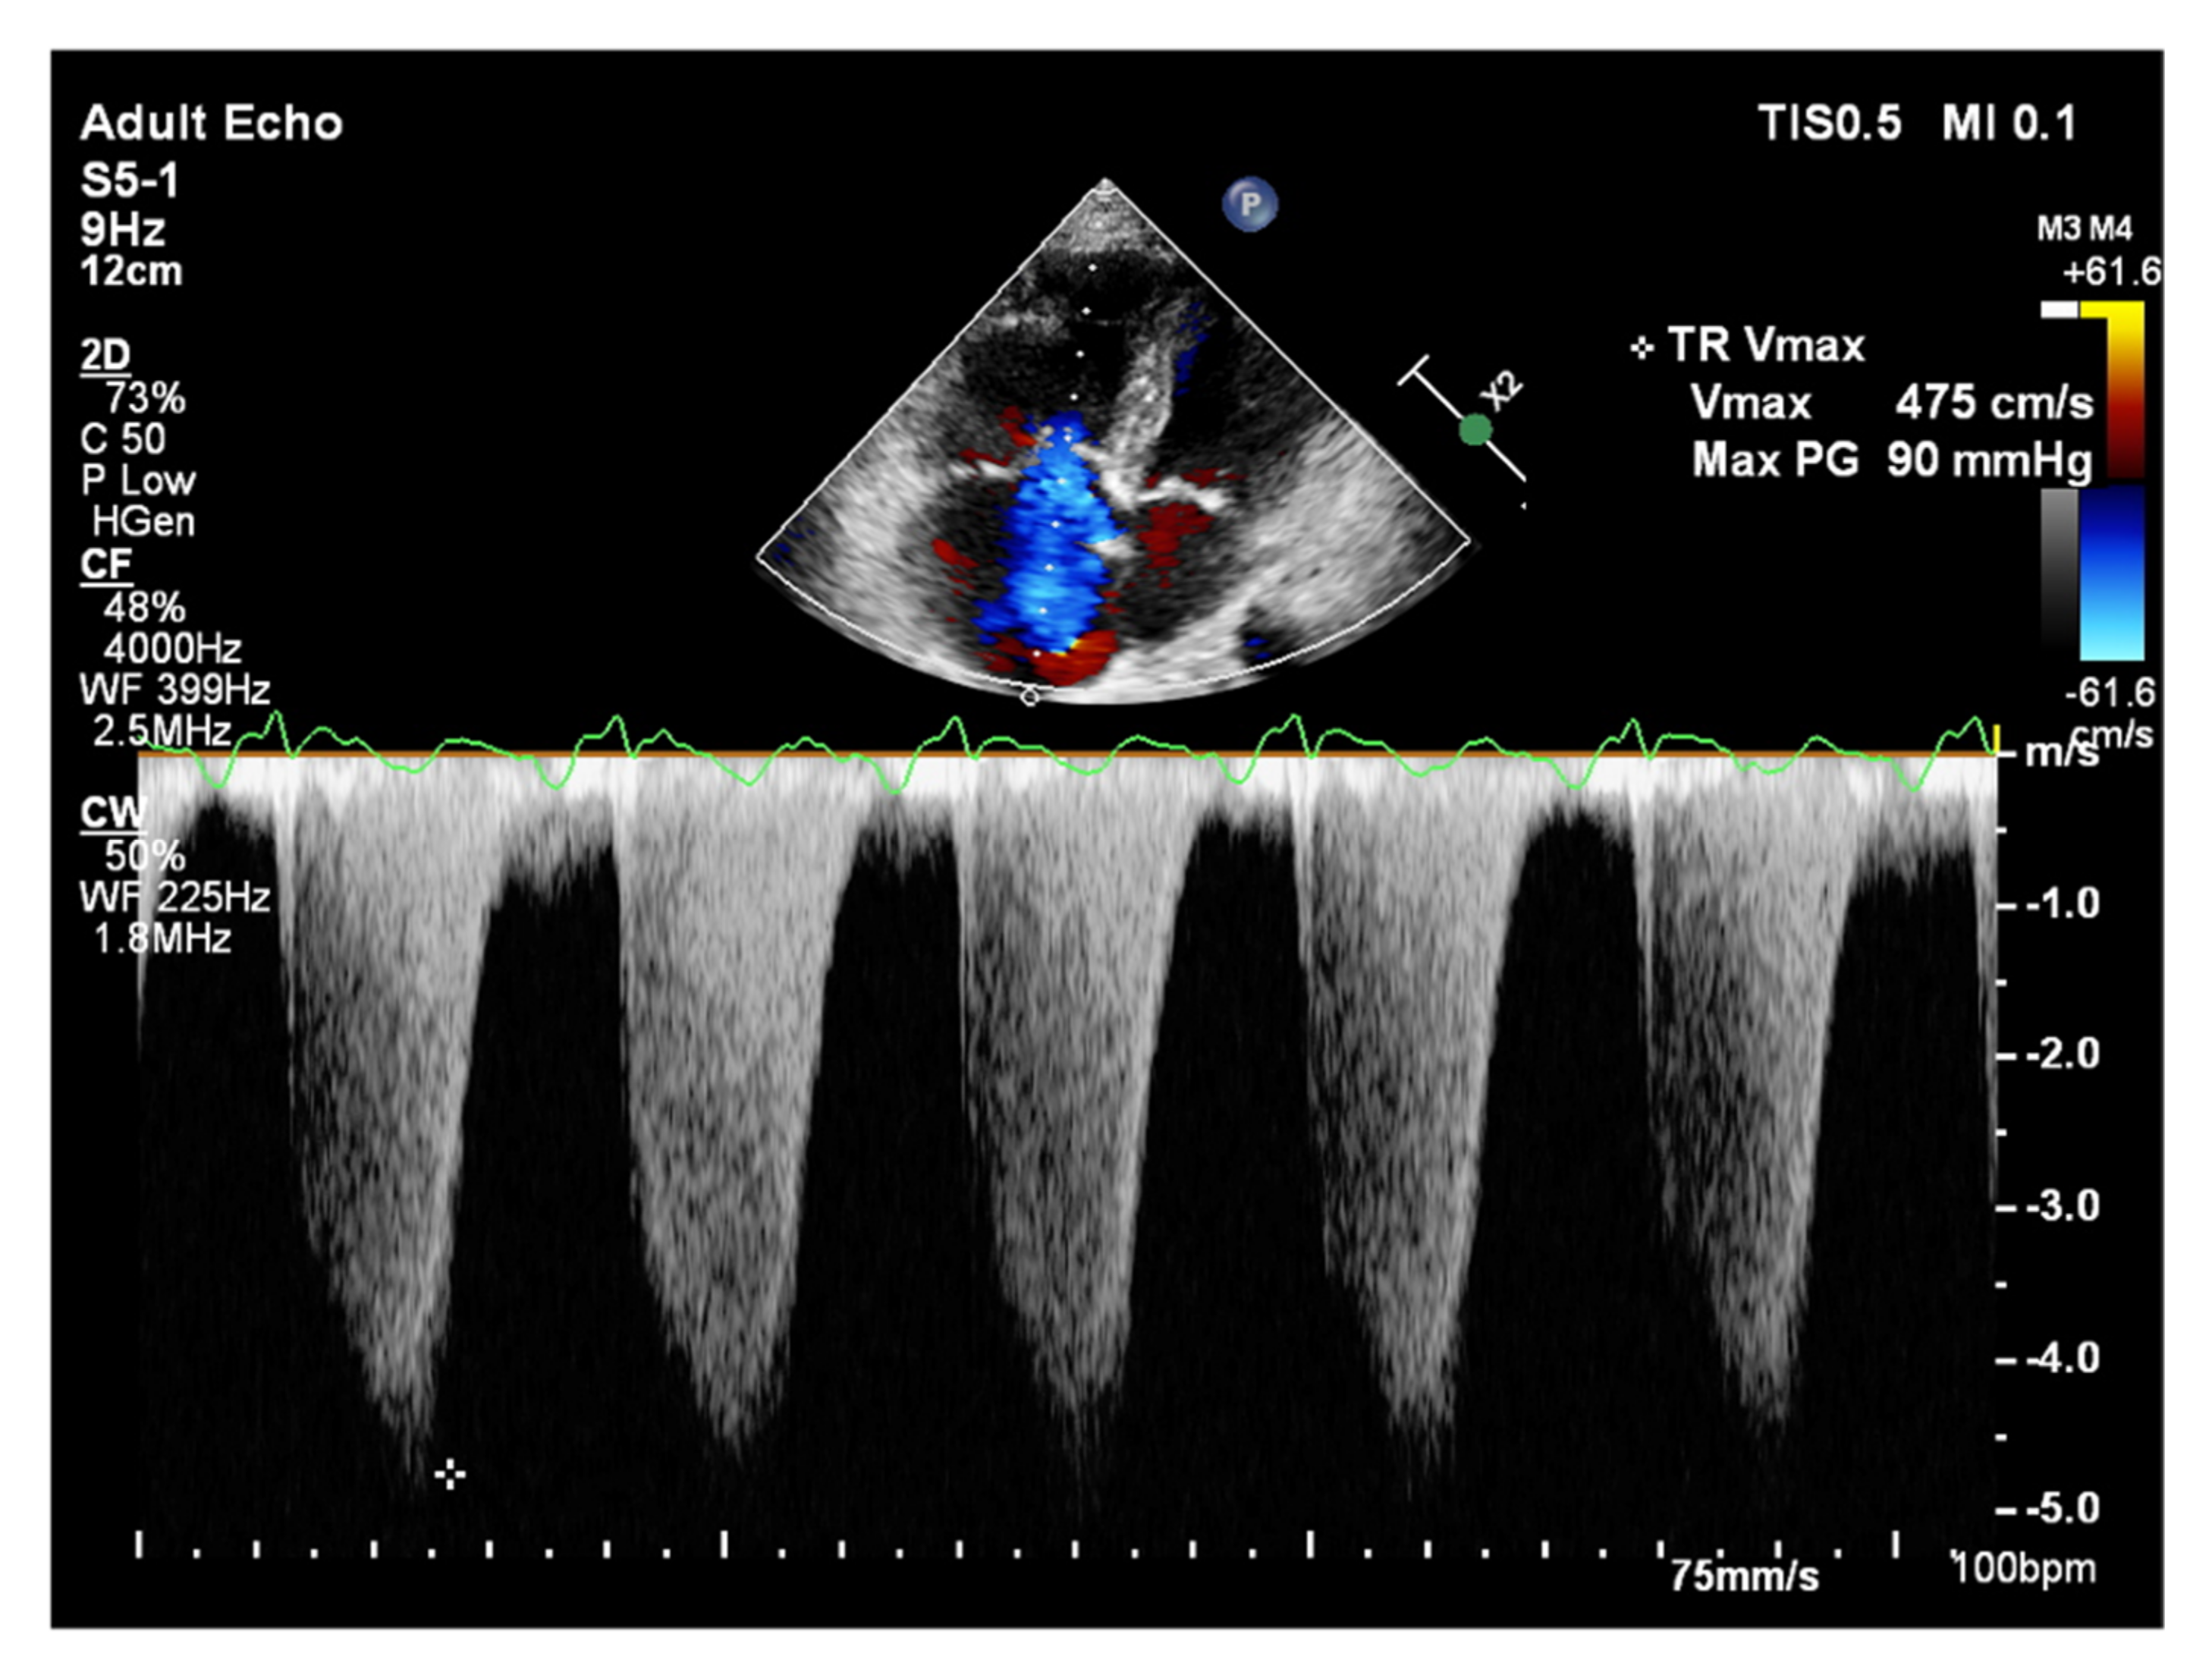

It is believed that if there is no RV outflow tract stenosis, the right ventricular systolic pressure (RVSP) is equal to the pulmonary artery systolic pressure (PASP) [70]. In everyday practice, the calculation of PASP is based on a simplified Bernoulli equation applied to peak tricuspid regurgitation velocity (TRV). TRV should be measured in several views, aiming at the best image quality and maximum velocity in continuous-wave Doppler and avoiding excessive gain and artifacts (Figure 12 and Figure 13). According to the equation, PASP = 4 (TRV)2 + RAP [71,72]. In addition, based on the measurements of end-diastolic pulmonary regurgitant return wave velocity (PRVend), it is possible to estimate pulmonary artery diastolic pressure (PADP) using the PADP = 4 (PRVend)2 + RAP formula [73]. On the other hand, PASP and PADP values can be used to calculate approximations of mean pulmonary artery pressure (mPAP) using the mPAP = 1/3 (PASP) + 2/3 (PADP) formula [74]. Several other formulas for calculating mPAP can be found in the literature. Chemla et al. developed another method to calculate mPAP, according to the formula mPAP = 0.61 × PASP + 2 mmHg [75].

Figure 12.

Doppler assessment of tricuspid regurgitant velocity (TRV). TTE, 4CH view. TTE: transthoracic echocardiography; 4CH: four-chamber.